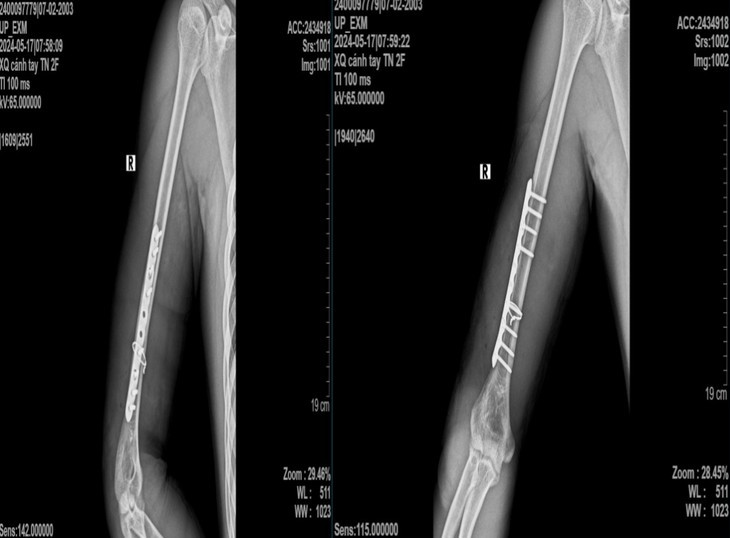

Bệnh nhân đến bệnh viện trong tình trạng sưng đau, biến dạng, hạn chế vận động cánh tay phải. Vận động bàn ngón tay bình thường, không yếu liệt, hình ảnh x-quang cho thấy xương cánh tay phải gãy chéo vát ở 1/3 dưới có mảnh rời cánh bướm lớn.

Ngày 14/5/2024, khi đang chơi vật tay cùng bạn thì đột nhiên thấy tiếng “cục” và sau đó đau chói, biến dạng, mất vận động cánh tay phải. Sau khi nhập viện, bệnh nhân được chẩn đoán: Gãy kín xương cánh tay phải không liệt quay, chỉ định phẫu thuật kết hợp xương nẹp vít.

Sau phẫu thuật kết hợp xương nẹp vít, người bệnh được chụp x-quang kiểm tra sau mổ, giải phẫu xương cánh tay được phục hồi, người bệnh ra viện sau 4 ngày.